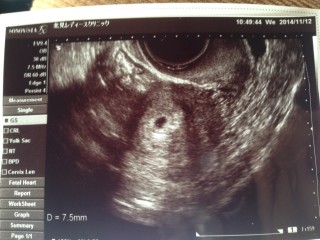

5w3d先週の初診では、胎嚢は確認出来ませんでしたが、この日無事に確認出来ました!7.5mmで、正常妊娠でした。 今から愛しくて、パパも毎日ベビのいるお腹に手を当てながら寝るのが、日課です!次は、二週間後に、心音確認の為受診予定です! ちゃんと確認出来る事を楽しみにしてます。

エコー写真